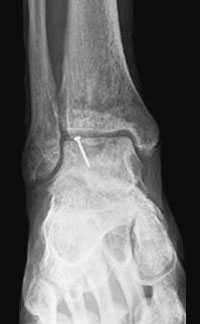

Не смотря на то, что Loomer с соавт. сообщили, что только от 50% до 66% остеохондральных дефектов обнаруживаются при помощи обычной рентгенографии, данный метод является важной отправной точкой и может быть полезен для исключения другой патологии голеностопного сустава [20]. Рентгенологическое исследование голеностопного сустава должно включать переднюю, заднюю и в 3⁄4 внутренней ротации проекции. Все проекции выполняются стоя (под нагрузкой) и называются функциональными. Функциональные рентгенограммы могут быть полезны для выявления сопутствующей нестабильности голеностопного сустава, проекция 3⁄4 во внутренней ротации, помогает в визуализации щели межберцового синдесмоза, а так же отображает передне-внутрений импижмент (таранной и большеберцовой кости) в случае его наличия. Выполненные в положении подошвенного сгибания прямая и 3⁄4 проекция во внутренней ротации могут быть полезны в выявлении заднемедиального поражения таранной кости. Рентгенологические признаки, которые могут быть определены, варьируются от небольших участков сдавления субхондральной кости до крупных отслоенных остеохондральных фрагментов. Радиографическая

система классификации была разработана Berndt и Harty в 1959 году и остается золотым стандартом. (Табл. 1) [16]. Loomer с соавторами дополнили имеющуюся классификацию, на основе не только рентгенограмм, а также МРТ (магнитно-резонансная томография) и КТ (компьютерная томография), и добавили стадию V в систему классификации Berndt и Harty [22].

МРТ является ценным инструментом в комплексе диагностики ОХПТК для оценки отека костной ткани, а также выявления скрытых повреждений субхондральной кости и хрящевого покрытия, которые могут быть пропущены при стандартных рентгенограммах или даже КТ. МРТ – самый лучший инструмент оценки для определения стабильности и жизнеспособности фрагмента таранной кости при его отслоении и эта информация может быть решающей в тактике выбора того или иного метода хирургического лечения. Однако, для определения размеров отслоившегося фрагмента таранной кости наилучший метод КТ, так как данные размеров по МРТ могут не соответствовать действительности в сторону переоценки последних. Hepple с соавторами изучив многочисленные данные МРТ диагностики разработали систему классификации ОХПТК на основе этого метода (Табл. 2) [23]. Однако, наиболее широко принятая система классификации, основанная на КТ-это классификация Ferkel и Sgalione (Табл. 3; Рисунок 4) [24]. Классифицировать ОХПТК также возможно выполнить интраоперационно, на основе артроскопических данных о состоянии остеохондрального поражения. Наиболее широко используется система Ferkel/Cheng (Табл. 4) [25], эта система классификации, в отличие от обычных рентгенограмм, КТ и МРТ, лучше всего взаимосвязана с исходами лечения пациентов.

Рентгенография

Рутинное рентгенологическое исследование включает рентгенографию обоих голеностопных суставов в прямой и боковой проекциях. На рентгенограммах можно увидеть отслоенный костный фрагмент. Изначально, на начальных стадиях болезни, площадь повреждения может быть очень мала, в связи с чем она не будет видна на рентгенограммах. Иногда изменения становятся видны только при рентгенологическом исследовании в динамике.